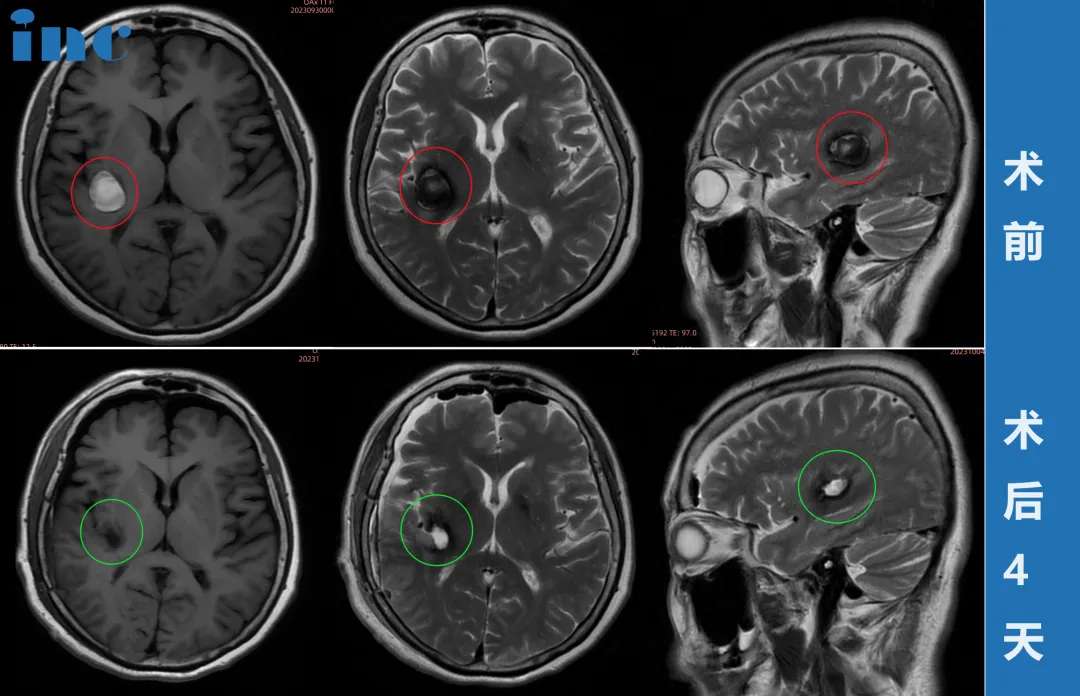

68岁女性•右侧基底节海绵状血管瘤术后8天出院

术前症状:多次出血,对于脑干海绵状血管瘤患者来说,是最不愿意看到的情况。而对于一个60多岁的基底节海绵状血管瘤患者来说,对手术这个合适的解决方式犹豫不决。68岁的柯女士,突然舌头麻木,晨起后出现眩晕,医院检查后结论为椎体骨质增生及脑供血不足。2022年再次进行手术去医院行核磁检查后发现海绵状血管瘤,医生建议定期复查MRI。然而含血病灶逐年增大,从22年的18*19mm到2023年的24*19mm,但是多名专家表示不赞成手术治疗,更是明确表示术后偏瘫失语可能性大。远程咨询INC巴特朗菲教授之后,教授给出了非常积极的评估。柯女士和家人商量后原本想要等巴教授下一次来华时再进行手术,然而谁也没想到9月底教授在华手术期间柯女士症状开始出现波动,发作频繁,当巴教授查看最新核磁图像后,发现病灶较前增大,结合患者病情有进展,告知患者随时会有出血风险,需要立即手术。柯女士和家人与巴教授紧急视频沟通之后,决定提前手术,果断买飞机票来到苏州。

治疗过程:在苏州大学附属第四医院,巴教授顺利完成手术,无任何新发神经功能损伤。

术后情况:术后第2天巴教授查房时,柯女士精神状态非常好,已经可以下地走路。看到前来查房的巴教授,柯女士非常激动,亲切拥抱感谢巴教授,终于摆脱了危险的基底节海绵状血管瘤的她满怀感激得握住巴教授的手说道,“我一定要看看巴教授这双神奇的大手,巴教授非常感谢你!”